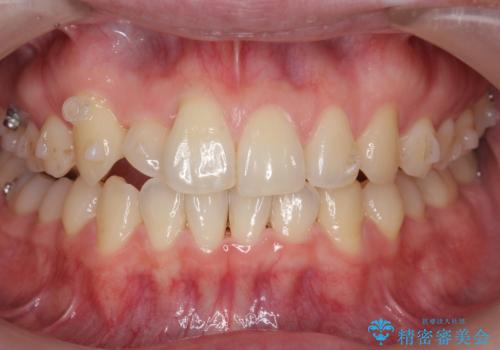

引っ込んだ前歯を並べる 歯を抜かないマウスピース矯正

- 右上の前歯が内側に入っているのを気にして来院。

右上の奥歯を後ろに移動して、前に出すスペースを確保してから並べました。

奥歯を後ろに送るために、矯正用インプラントを使用しています。

前歯が内側に入っていると、笑った時にそこが黒くなり、歯が抜けたように見えます。

口を開けたとき、笑顔の印象が大きく変わり、大変喜んでいただけました。